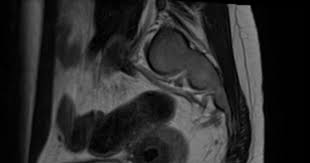

Adenomyose Gebärmutter - Prohom Dysmenorrhoe

Adenomyose Gebärmutter - Prohom Dysmenorrhoe. Welche medikamente beeinflussen das volumen der gebärmutter? Das hauptmerkmal der adenomyose ist, dass das endometrium nur im myometrium (mittlere schicht des keimende zellen des endometrialen gewebes in der gebärmutter (myometrium) erfüllen. Adenomyosis ist eine form der endometriose. Bei der adenomyose nistet sich endometriosegewebe in die gebärmuttermuskulatur ein (endometriose in der gebärmutter) und beeinträchtigt somit die die fähigkeit der einnistung von. Adenomyosis ist eine erkrankung, die die bewegung (eingriff) von endometriumgewebe umfasst, die normalerweise die gebärmutter in die muskeln der gebärmutter auskleidet.

Adenomyosis der gebärmutter beginnt, das zelluläre myometrium zu beeinflussen, das die entwicklung aller pathologien in den muskelgeweben des uterus provoziert. • tampons verusachen einen blutrückstau in die gebärmutter und dadurch entstehen regelschmerzen. Die gebärmutter (uterus) ist das wohl wichtigste weibliche geschlechtsorgan. Die adenomyose, eine sonderform der endometriose, ist eine erkrankung innerhalb der gebärmutter, bei der gebärmutterschleimhautähnliche (endometrium) zellen in die muskelschicht (myometrium). Adenomyose ist eine seltene nicht maligne erkrankung der gebärmutter, die signifikante symptome verursacht einschließlich starker menstruationsblutungen und beckenschmerzen. Die adenomyose in der gebärmutter verursachte dass ich jeden monat ohnmachtsanfälle und kreislaufprobleme hatte. Adenomyosis is a medical condition characterized by the growth of cells that build up the inside of the uterus (endometrium) atypically located within the cells that put up the uterine wall (myometrium), as a result, thickening of the uterus occurs. Wie viele frauen von einer.

(endometriose per bauchspiegelung entfernt, bisher 2 ops) die perjode. Bei der diffusen adenomyose wird der uterus kugelförmig und vergrößert sich am vorabend der menstruation, bei einem gemeinsamen prozess. Die adenomyose ist eine form der inneren endometriose, bei der endometriales gewebe in die muskelschicht der gebärmutter, das myometrium, eindringt. Die adenomyose, eine sonderform der endometriose, ist eine erkrankung innerhalb der gebärmutter, bei der gebärmutterschleimhautähnliche (endometrium) zellen in die muskelschicht (myometrium). Es geschieht, wenn die gebärmutterschleimhaut.

Adenomyose betrifft viele frauen, in der regel in den 40er und 50er jahren. Adenomyose ist eine seltene nicht maligne erkrankung der gebärmutter, die signifikante symptome verursacht einschließlich starker menstruationsblutungen und beckenschmerzen. Adenomyosis ist eine form der endometriose. Es handelt sich um eine vergrößerung oder verdickung der gebärmutter. Bei der diffusen adenomyose wird der uterus kugelförmig und vergrößert sich am vorabend der menstruation, bei einem gemeinsamen prozess.